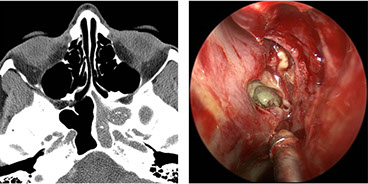

Nasopharyngeal Angiofibroma (NPAF)

- formerly juvenile angiofibroma

Uncommon, highly vascular c HPC pattern (horny vessels), b9 but aggressive and can be fatal (in 1/20)

- seen in teens, M>F (almost exclusively in males), before 25 yo, arise in posterior nasal cavity

- pts get epistaxis, headaches, nasal obstruction, proptosis, anosmia, nasal discharge

- Imaging: inc vascularity, possible erosion of bone and intracranial invasion

Gross: pink polypoid mass

micro: looks like has collagen coming off vessel

- big open vessels in collagenous stroma c fibroblasts and myofibroblasts (appear stellate and spindly)

- the tissue will usually have been embolized and lost its characteristic patterns

IHC: (+) B-catenin

Gene: del cr 17 in p53 and Her-2/neu regions

Tx: excision

Px: b9 but locally aggressive